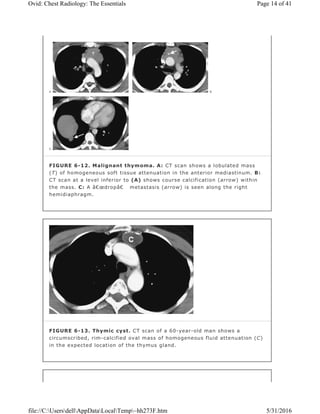

FIGURE 6-12. Malignant thymoma. A: CT scan shows a lobulated mass

(T) of homogeneous soft tissue attenuation in the anterior mediastinum. B:

CT scan at a level inferior to (A) shows course calcification (arrow) within

the mass. C: A “drop†metastasis (arrow) is seen along the right

hemidiaphragm.

FIGURE 6-13. Thymic cyst. CT scan of a 60-year-old man shows a

circumscribed, rim-calcified oval mass of homogeneous fluid attenuation (C)

in the expected location of the thymus gland.

symmetric and maintains a somewhat triangular shape on axial imaging. Invasive

thymomas inhabit the mediastinal fat, spreading to the pericardium and pleura.

Unless mediastinal invasion has occurred, distinguishing benign from invasive

thymoma is not possible with CT scanning. Transpleural spread may manifest as

so-called “drop metastases†at a site distant from the primary lesion (Fig.

6-12), and imaging of the entire pleural space and upper abdomen is therefore

important. Extensive pleural involvement may mimic malignant mesothelioma.

Other less common thymic masses include cyst (Fig. 6-13), abscess,